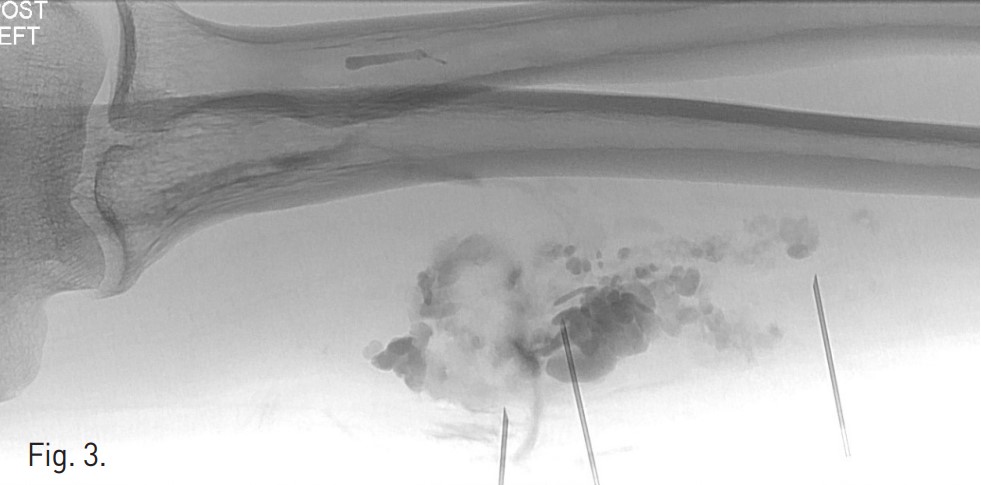

Venography demonstrates dilated, tortuous veins along the medial aspect of the proximal forearm draining into normal veins (Fig. 1). Negative digital subtraction angiography shows filling-defects from displaced contrast material in the vascular malformation during sodium tetradecyl sulfate foam injection (Fig. 2). A native image of the forearm demonstrates stasis of contrast material within the venous malformation after foam sclerotherapy (Fig. 3). T2 STIR imaging shows a 10.3 x 2.5 x 2.3 cm high signal intensity mass centered within the flexor digitorum superficialis consistent with slow-flow vascular malformation. The high signal represents the extent of the vascular malformation as well as post-treatment edema or inflammation (Fig. 4). Post-contra st T1 imaging with fat suppression demonstrates heterogeneous enhancement of the mass with notable areas of low signal representing the areas of thrombosis/sclerosis. The residual irregular enhancement represents postprocedural inflammation. Of note, there are no enhancing serpiginous structures (Fig. 5).

Fig. 3.

Fig. 3. A native image of the forearm demonstrates stasis of contrast material within the venous malformation after foam sclerotherapy.